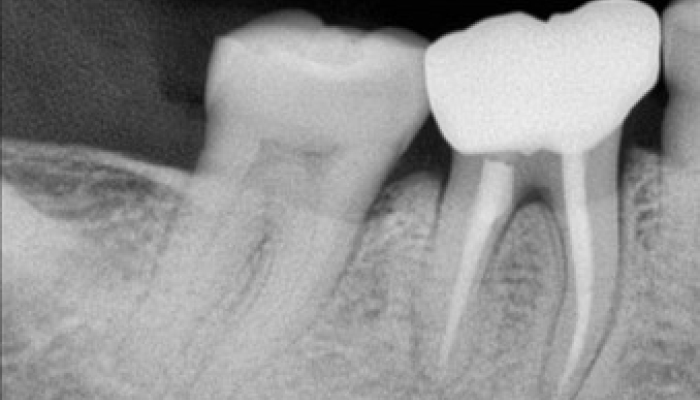

충치치료 전후 사례

• 치료 전

치료 후